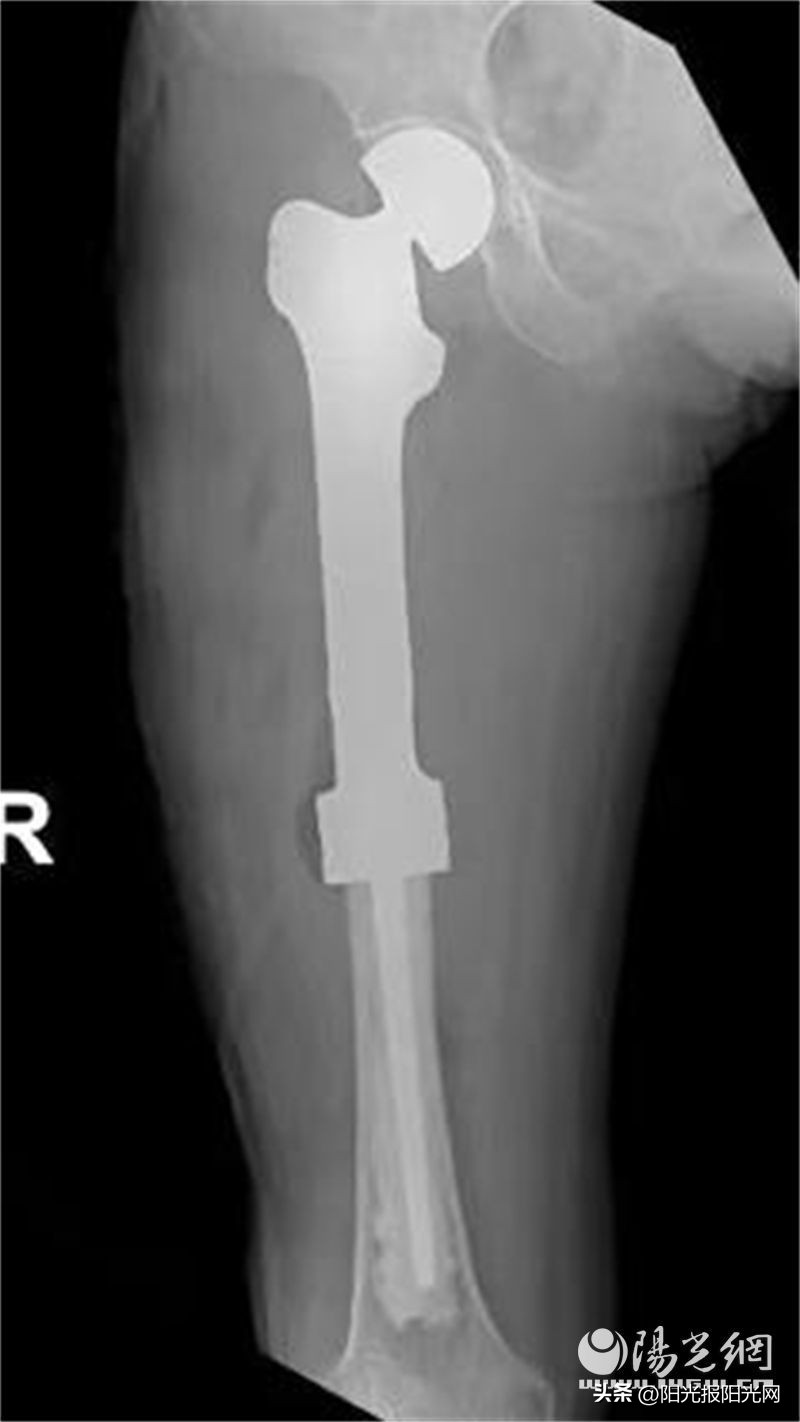

患者术后没有任何不适,恢复良好,未输血。术后拍片显示3D打印假体按计划植入,髋臼匹配良好。术后3天患者可坐起,术后1周患者可下地行走功能锻炼,术后2周可基本自主扶拐活动。2周间断拆线后出院。

恶性骨肿瘤的手术及关节重建是骨科手术的难点和雷区,3D打印定制假体治疗一般都是国内著名三甲医院骨肿瘤科开展,花费也比较贵。借助3D打印,以及邢科主任较早对此领域积累的技术力量,该院骨外科三病区让患者两次住院花费合计不到5万元即完成了这种个性化设计和治疗。过去对于普通家庭遥不可及的新科技治疗手段,在该院和科室的共同努力下正在让越来越多的群众受益。